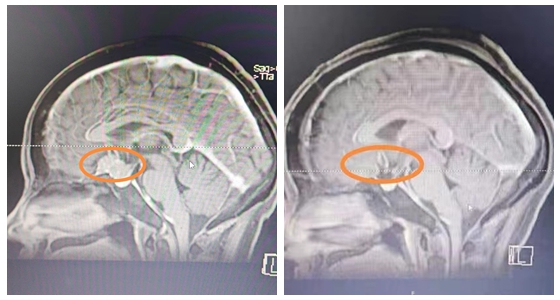

近日,湘雅常德医院神经外科团队成功为来自山东的王女士切除6*5.5*5.2cm大小的巨大岩斜坡区脑膜瘤。     年仅40多岁的王女士因头晕、左侧听力下降,检查出脑肿瘤10年余,一...